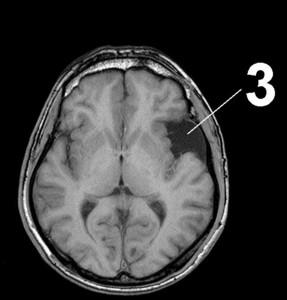

МР-томограммы головного мозга.

1. Киста, возникшая после кровоизлияния в мозг.

2. Кисты мозжечка, возникающие вследствие ишемического инсульта (закупорка сосудов головного мозга).

3. Кистозно-слипчивый арахноидит.